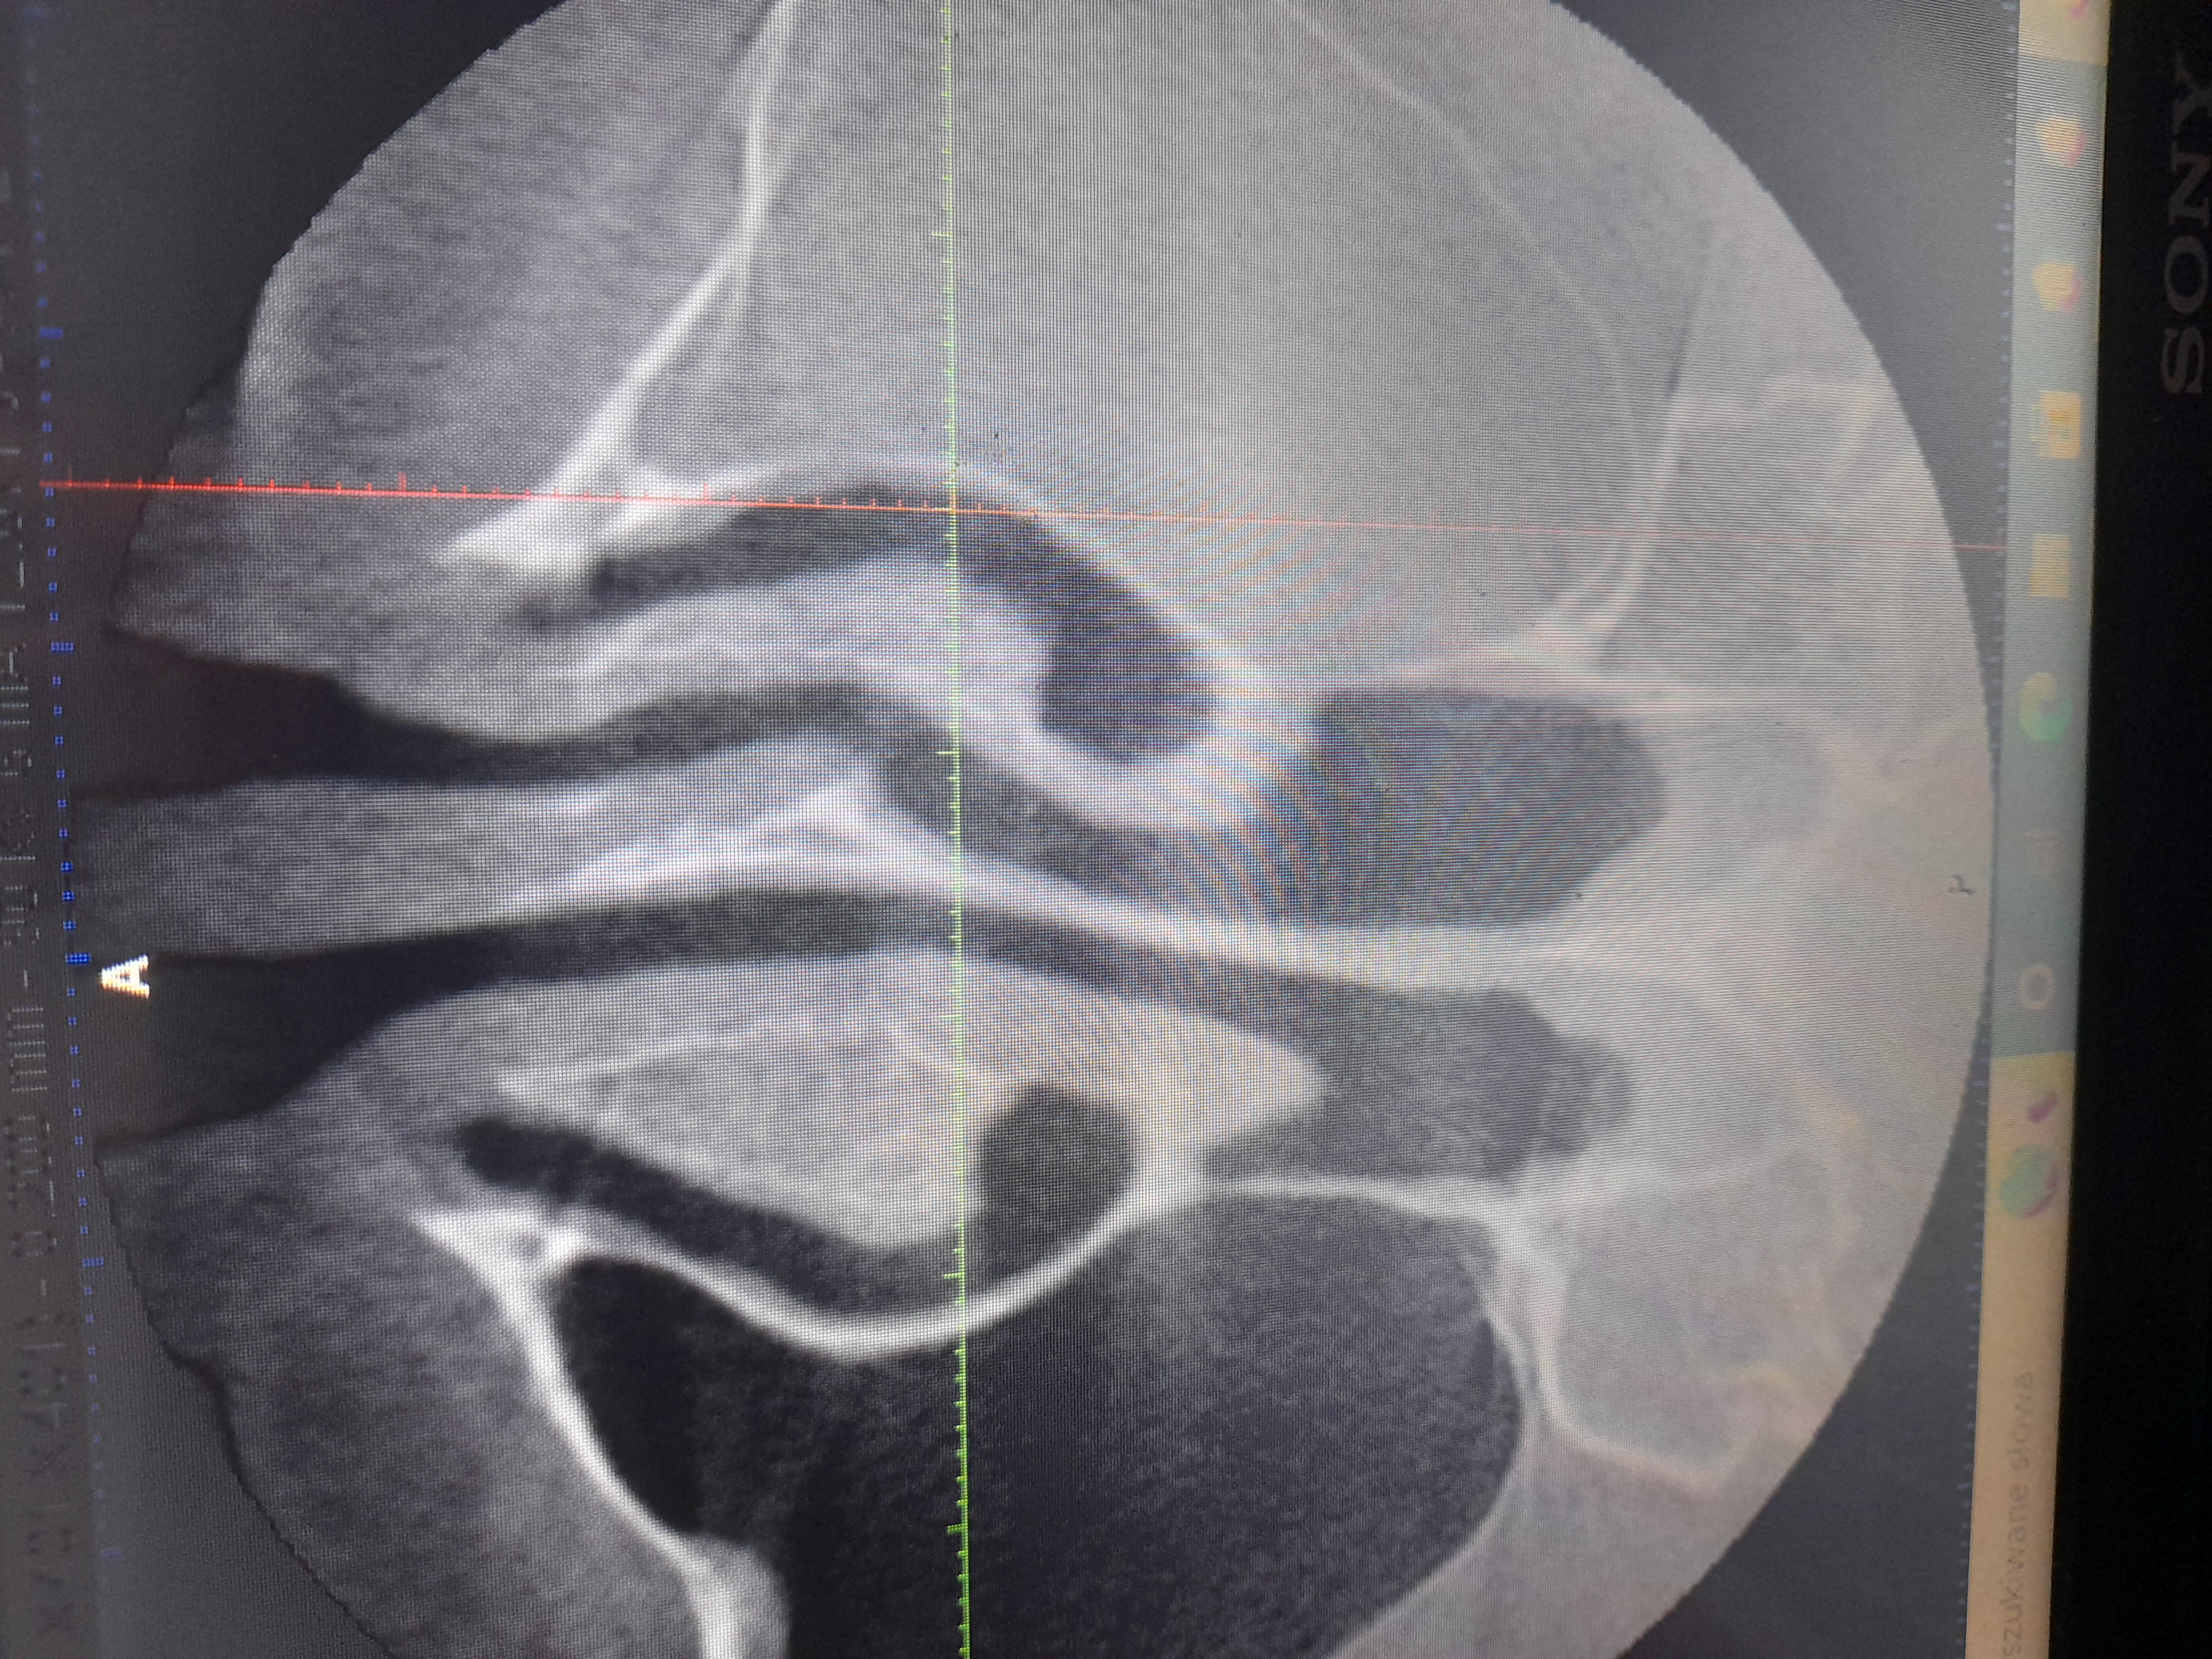

Polipowate zgrubienie śluzówki całej lewej zatoki szczękowej

1 kwietnia wydzlo mi polipowate zgrubienie slozowki calej lewej zatoki szczekowej a w prawej w zachylku zebodolowym 15 mm. Jeden mi powoedzial lekarz ze to wydzielina. Bralam sterydy dwa miesiace i nadal to samo. Boje sie ze jak mam.cala taka lewa zatoke zawalona jakimis zmianami i jakby plynem bo ci lekarze a bylam u kilku nie wiedza czy czasem tam plynu nie ma to wreszcie dostane sepsyalbo czegos gorszego raka lub ze te zmiany zniszcA mi kosci w zatoce. Wysylam zdjecie. Ktos pomoze?